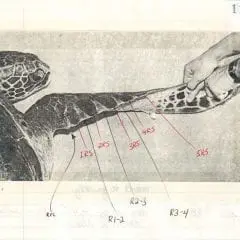

2012- Photo Depictions of Auto-Grafting a Juvenile Green Turtle.